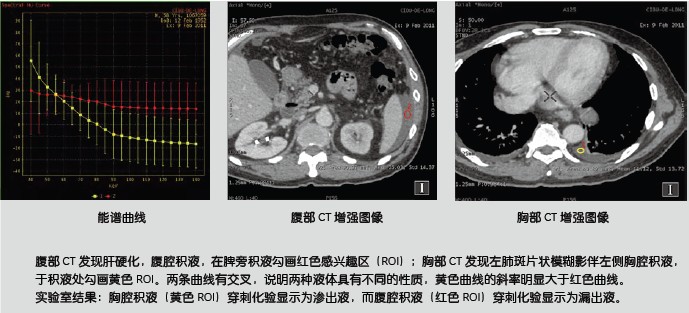

能谱曲线体现了不同物质对X线的吸收程度,从而体现了物质本身的结构特性。从以下的糖水及盐水的例子可以看出,在常规CT上表现为同样CT值-即无法区分的糖盐水却表现为完全不一样的能谱曲线,从而让我们可以区分它们。

同样,对于常见的胸水的病理类型为渗出液还是漏出液,也可以通过能谱曲线进行鉴别。

ROI 1(低灌注区): 碘的物质浓度1.40mg/ml

ROI 2(同侧肺对照区)碘的物质浓度3.07mg/ml

ROI 3(对侧肺同区域)碘物质浓度 3.84mg/ml

宝石能谱CT开创了CT定量分析的新时代。